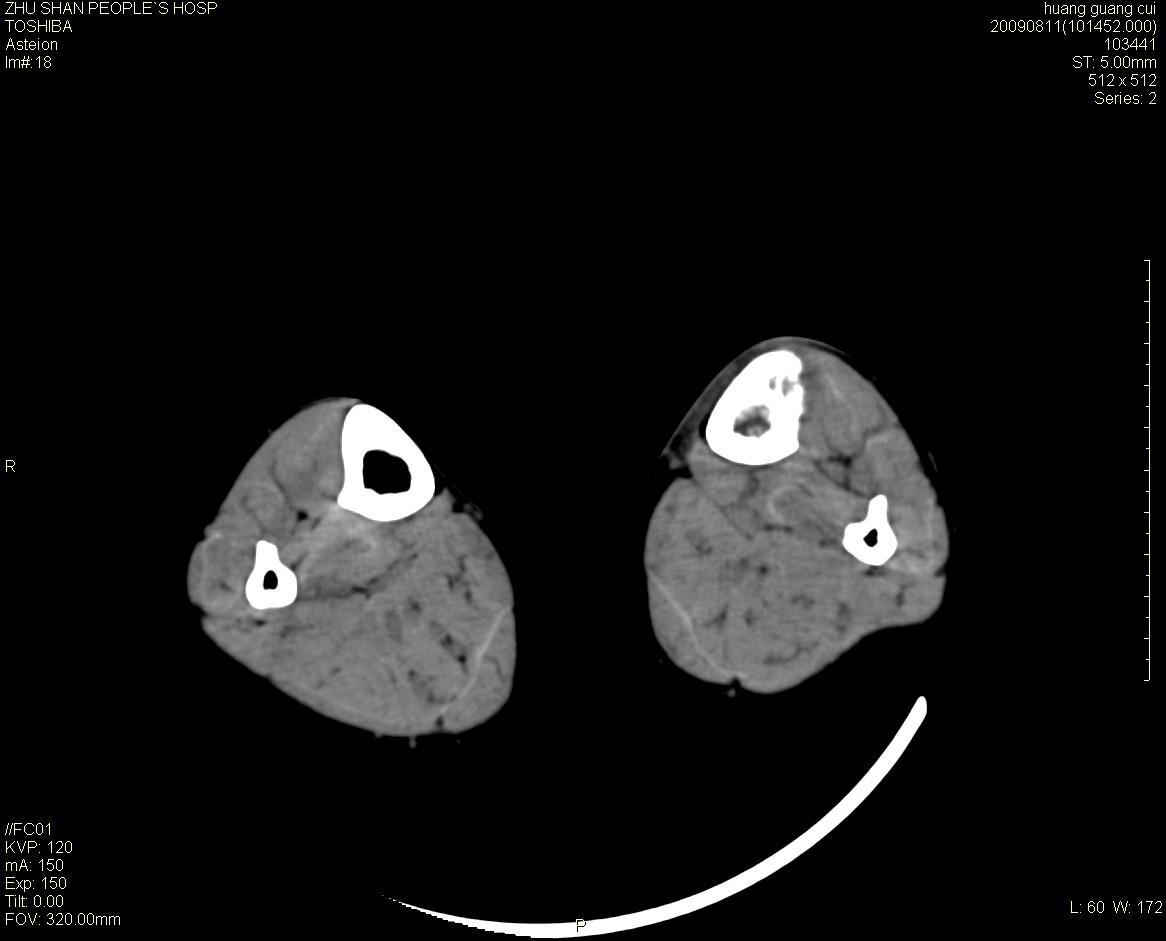

标题: CT21557:女性 56岁 左胫骨中断肿痛2月余。 [打印本页]

标题: CT21557:女性 56岁 左胫骨中断肿痛2月余。

女性 56岁 左胫骨中断肿痛2月余。转移瘤or尤文氏肉瘤?

左侧胫骨中段骨皮质溶骨性破坏,髓腔内外见软组织肿块,无明显钙化及成骨,定位相显示病变周围“筛孔样”改变,定性恶性无疑,原发或转移均有可能,倾向于骨纤维肉瘤可能性大,转移瘤不排除。膝关节以下骨转移很少,且要有原发灶支持,尤文氏肉瘤年龄太大不支持。